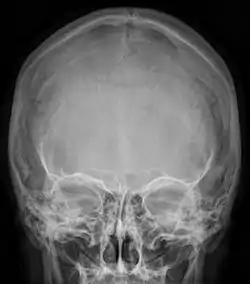

![]() Radiograph of the skull showing an interparietal bone between the occiput and parietal bones | |

An interparietal bone (os interparietale or Inca bone or os Inca. Var.[1]) is a dermal bone situated between the parietal and supraoccipital. It is homologous to the postparietal bones of other animals.

In humans, it corresponds to the upper portion of the squama of the occipital bone that lies superior to the highest nuchal line and is completely fused to the supraoccipital. However, in some individuals this portion remains separate from the rest of the occipital bone throughout life. In such cases, this separate bone is particularly referred as Inca bone. Inca bones in humans were first found in the skulls of contemporary indigenous peoples of the southern Andes as well as in those of mummies of the Inca civilization. Although the Inca bone was originally encountered as a variation in South American and Latin American cranial remains, the variation occurs in people from all geographic regions of the world and is by no means indicative of South/Latin American origin.